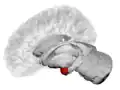

Left lateral view of the amygdala in an average human brain